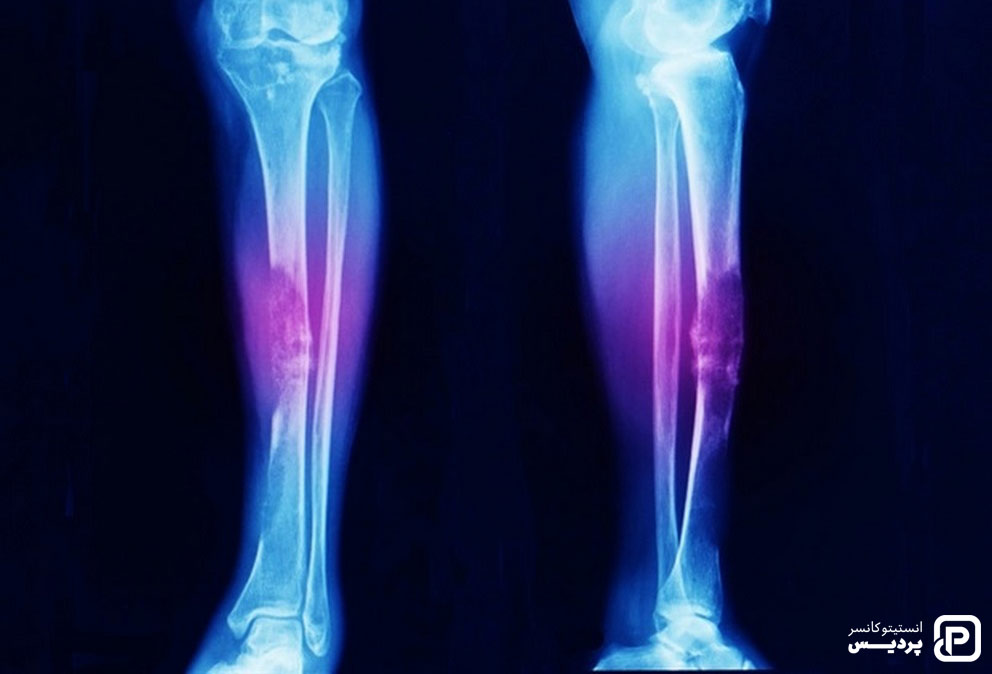

سرطان های استخوان

سرطان هایی که از استخوان شروع می شوند (سرطان های اولیه استخوان) اغلب در کودکان بزرگ تر و نوجوانان اتفاق می افتد، اما در هر سنی ممکن است ایجاد شود. این نوع سرطان حدود 3 درصد از سرطان های دوران کودکی را تشکیل می دهد. دو نوع اصلی از سرطان های اصلی استخوان در کودکان رخ می دهد:

استئوسارکوم در نوجوانان شایع است و معمولاً در مناطقی که استخوان به سرعت در حال رشد است، مانند نزدیکی انتهای استخوان های پا یا بازو ایجاد می شود. این بیماری اغلب باعث درد استخوان می شود که شب هنگام یا با فعالیت بدتر می شود. همچنین، می تواند باعث تورم در ناحیه اطراف استخوان شود.

سارکوم Ewing نوعی از سرطان استخوان است که کمتر شایغ می باشد. این نوع سرطان اغلب در نوجوانان دیده می شود. متداول ترین مکان ها برای شروع آن، استخوان های لگن، دیواره قفسه سینه (مانند دنده ها) یا در وسط استخوان های پا می باشد. علائم می تواند شامل درد و تورم استخوان باشد.